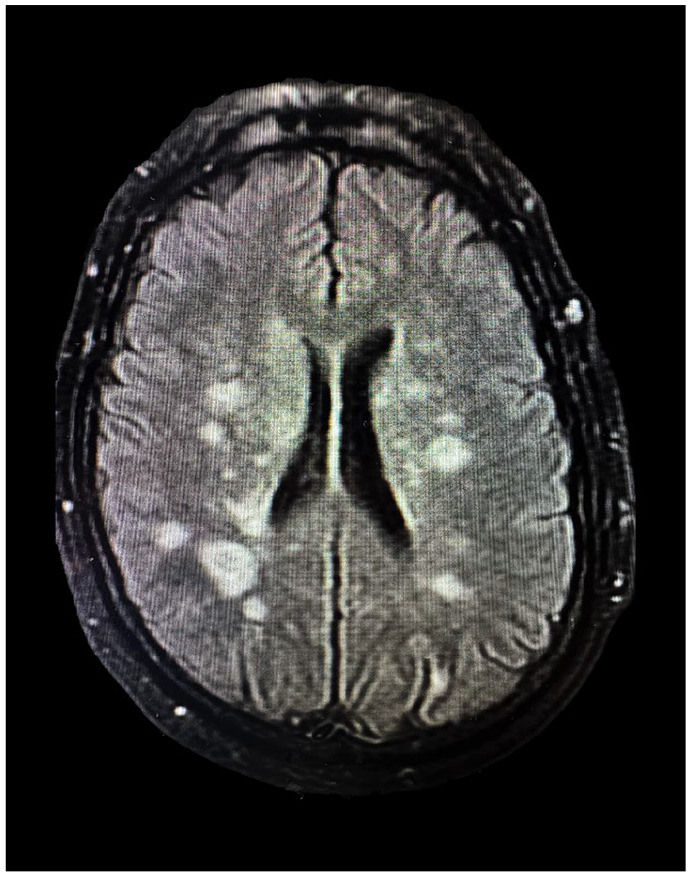

Nontraumatic clostridial myonecrosis infections are predominantly caused by Clostridium septicum. Most patients have an underlying gastrointestinal malignancy. This case presents a rare association of spontaneous clostridial myonecrosis preceding cerebral septic emboli with underlying invasive colorectal adenocarcinoma. A 60-year-old male with a history of hypertension, diabetes, and a family history of colon cancer presented to the emergency room with worsening left-sided chest pain radiating to his left shoulder. Extensive workup revealed elevated D-dimer, troponin, C-reactive protein, white blood cell count, and creatinine phosphokinase. Due to his clinical signs, symptoms, elevated white count, and further decompensation, he was started on antibiotics for sepsis. Physical exam revealed left upper extremity (LUE) crepitus consistent with imaging of innumerable soft tissue gas collections along the LUE. Incision, drainage, and myomectomy were performed due to concerns of myositis and necrotizing infection. Muscle biopsy revealed myonecrosis, and subsequent samples were positive for C. septicum. Postoperative pressor support and several sessions of surgical debridement were required. He continued to deteriorate and developed left-sided paralysis. Computed tomography head revealed several white matter infarcts indicative of septic emboli. The patient slowly recovered neurologically after switching to central nervous system-penetrating antibiotics. Months later, a colonoscopy revealed cecal adenocarcinoma. This case features a unique course of spontaneous C. septicum infection. There are high mortality rates, and previous studies report an association with colorectal malignancies. Therefore, preventative and diagnostic evaluations are imperative with a confirmed C. septicum infection. To our knowledge, this is the first case reported of cerebral septic emboli secondary to spontaneous myonecrosis with C. septicum, highlighting a unique burden of emboli-induced neurological deficits.